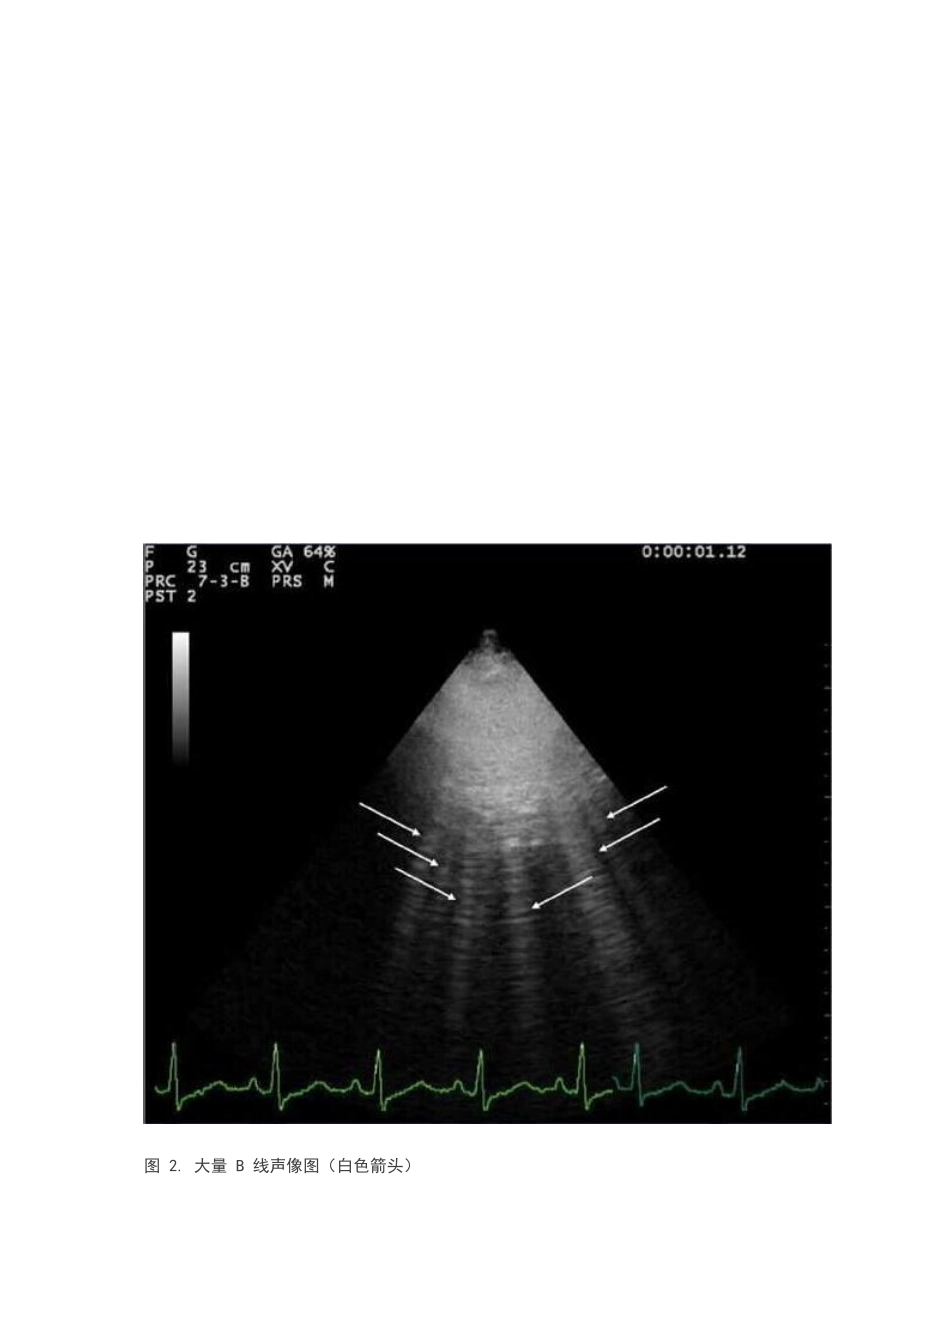

手把手教程:肺部超声检查2024-03-09 11:52 来源:丁香园作者:丁钱山字体大小-|+在过去几年里,一种新的超声成像应用在临床上出现:肺部超声(LUS),从传统胸腔积液的有无及定量评估,已经革命性地走向了肺实质成像检查。尽管受到空气限制,但是肺部超声已经被证实对多种急慢性疾病的评估意义重大,从心源性肺水肿到急性肺损伤,从气胸到肺炎,从间质性肺疾病到肺梗塞和挫伤等等。另一方面,这项技术简单易学,技术方面很少受到限制,并且快速、便携、可重复、非电离性,适合在各种不同情况下的运用。多种优势下,未来几年内,肺部超声可能在各种不同的医疗环境中扮演着越来越重要的角色。什么是肺部超声在教科书中,肺部超声评估是局限性的,因为超声波在空气中急速消退,而肺内由于空气的存在,造成了肺内与周围实质组织间的回声失落,从而肺实质难以直接成像。正常充气的肺,唯一能被检测到的组织便是胸膜,显示为一条高水平线,称胸膜线。但是究竟这条线是由于肺泡气和胸壁软组织之间的反射影假象还是实时胸膜的影像,尚存在争议。胸膜线随着呼吸进行同步运动:这种动态水平运动称作肺滑动。此外, 还有一些高回声水平线定期从胸膜线出现:称 A 线,与肺滑动相结合时, 这些混合回声代表着肺泡中正常或过度充气的内容(图 1)。当空气含量降低时,一些渗出液、漏出液、胶原及血液等会使肺密度增加,肺与周围组织之间的回升失落效应也便减少了,超声便能一定程度上反应更深区域的影像。这种现象会产生一些垂直混合回声称 B 线(图 2)。B 线影即在腹部超声中常见的“彗尾征”。B 线在专家达成一致的命名意见前也称“彗尾征”或“肺超彗尾征”。B 线是从胸膜线出现延伸至屏幕底部的离散垂直混响伪像影,不发生失落,与肺滑行同步运动。超声示大量 B 线影是肺间质综合征的征象,其数量随着空气含量的降低和肺组织密度的增加而增多。当肺部含气量进一步降低,肺部组织实质化,声像可视为一个与肝脏和脾脏回声类似的实体组织(图 3)。肺实质化是一个进展性的结果,肺栓塞,肺内癌症转移,压迫或堵塞性肺不张和肺挫伤均能导致这种结果。边缘组织实质化,空气和液体的存在或血管融合等征象也进一步提示肺实质化。图 1. 含气肺声像图表现。箭头示 A 线。上述可见胸膜线与 A 线的水平运动、肺滑动。 图 2. 大量 B 线声像图(白色箭头)图 3. 肺实质化声像图。回声类似于肝脏。某些情况下,超声在含气器官诊断中的局限性又...